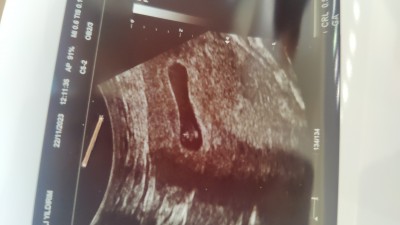

7 hafta 6 günlük gebelik kesem normal mi sizce arkadaşlar

Gebelik haftası 8